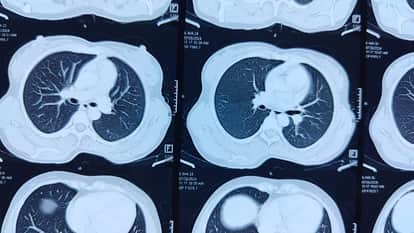

हाथरस जिला अस्पताल में महज एक रुपये के पर्चे पर होने वाले सीटी स्कैन की अहमियत मरीज और उनके तीमारदार नहीं समझ रहे। जिला अस्पताल में पिछले एक साल में 225 मरीज ऐसे हैं, जिन्होंने अपना सीटी स्कैन तो कराया, लेकिन उसकी रिपोर्ट लेने नहीं आए।

जिला अस्पताल में हर महीने औसतन 650 से 700 सीटी स्कैन किए जा रहे हैं। चौंकाने वाला तथ्य यह है कि इनमें से 15 फीसदी मरीज हर महीने अपनी रिपोर्ट काउंटर पर ही छोड़कर चले जाते हैं, जहां निजी सेंटरों पर इस जांच के लिए हजारों रुपये खर्च करने पड़ते हैं, वहीं सरकारी अस्पताल में मात्र एक रुपये में मिल रही इस सुविधा की कद्र नहीं की जा रही है।

अस्पताल प्रशासन का कहना है कि लोग इस सुविधा की अहमियत नहीं समझ रहे हैं। एक सीटी स्कैन पर सरकार का भारी खर्च आता है और स्कैन करने व रिपोर्ट के रखरखाव में स्टाफ की भी मेहनत लगती है। बता दें कि निजी जांच केंद्र पर हेड सीटी लगभग दो हजार रुपये, चेस्ट सीटी चार हजार रुपये और पेट का सीटी सात हजार रुपये में होता है।

- जांच शुल्क-मात्र 1 रुपया

- हर महीने होने वाले सीटी स्कैन-650 से 700

- रिपोर्ट न लेने वाले मरीज-15 प्रतिशत प्रति माह

- कुल लंबित रिपोर्ट-225